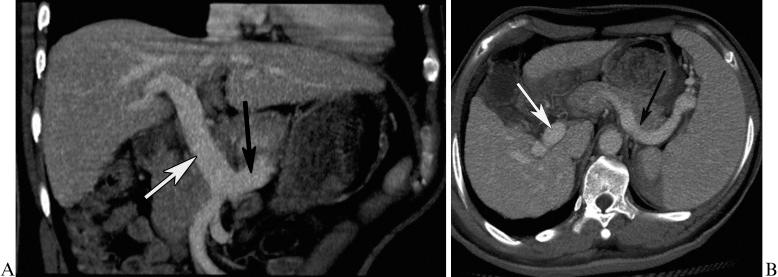

The aim of this study was to determine whether and how the diameter of the vein that gives rise to the inflowing vein of the esophageal and gastric fundic varices secondary to posthepatitic cirrhosis, as measured with multidetector-row computed tomography, could predict the varices and their patterns.

A total of 106 patients with posthepatitic cirrhosis underwent multidetector-row computed tomography. Patients with and without esophageal and gastric fundic varices were enrolled in Group 1 and Group 2, respectively. Group 1 was composed of Subgroup A, consisting of patients with varices, and Subgroup B consisted of patients with varices in combination with portal vein-inferior vena cava shunts. The diameters of the originating veins of veins entering the varices were reviewed and statistically analyzed.

The originating veins were the portal vein in 8% (6/75) of patients, the splenic vein in 65.3% (49/75) of patients, and both the portal and splenic veins in 26.7% (20/75) of patients. The splenic vein diameter in Group 1 was larger than that in Group 2, whereas no differences in portal vein diameters were found between groups. In Group 1, the splenic vein diameter in Subgroup A was larger than that in Subgroup B. A cut-off splenic vein diameter of 8.5 mm achieved a sensitivity of 83.3% and specificity of 58.1% for predicting the varices. For discrimination of the varices in combination with and without portal vein-inferior vena cava shunts, a cut-off diameter of 9.5 mm achieved a sensitivity of 66.7% and specificity of 60.0%.

The diameter of the splenic vein can be used to predict esophageal and gastric fundic varices and their patterns.